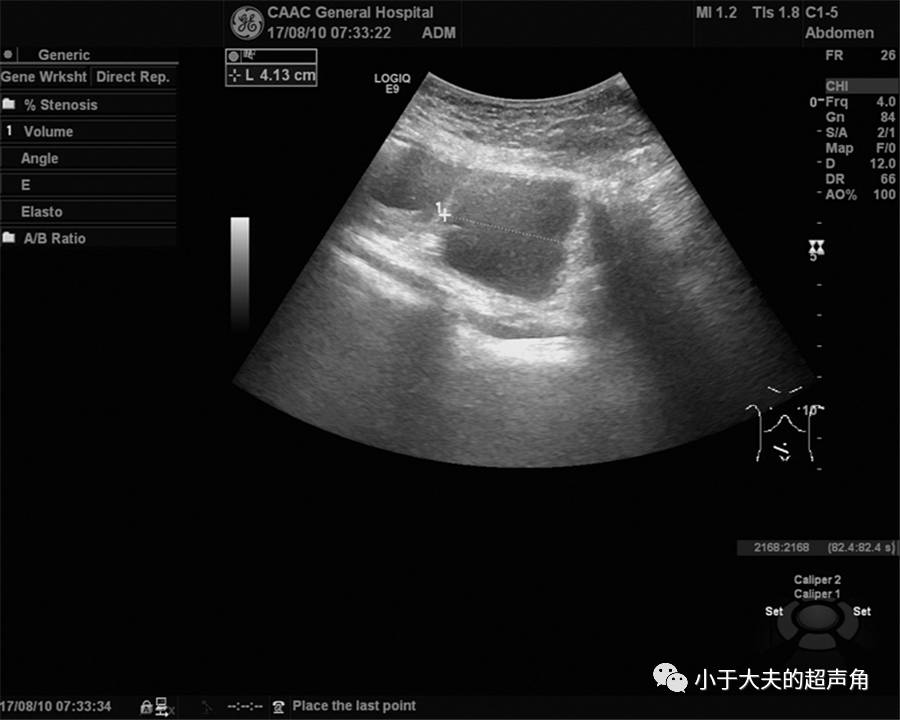

上图:果然,在紧邻肠管的既往手术切口处肌层内,发现不规则偏低回声,大小约4.2×3.0cm,边界模糊不清。

上图:既往切口深方另一处占位,边界模糊不清,内部回声减低不均。